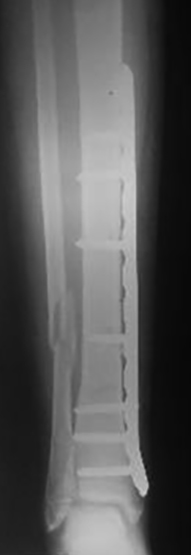

Se utilizaron placas bloqueadas LCP (Synthes, Paoli, PA) en seis pacientes y en dos pacientes placas de reconstrucción bloqueadas (Synthes, Paoli, PA) acorde al largo del hueso (placas largas). En una primera instancia se colocaron fijadores externos en las fracturas expuestas de seis pacientes. Se realizaron limpiezas quirúrgicas en promedio de 2 por paciente (rango: 1-5) y una vez que las partes blandas lo permitieron, se colocó la placa bloqueada. El tiempo promedio para la realización de la cirugía definitiva fue de 8 (rango: 3 - 25) días. En cuatro pacientes se realizó un abordaje antero-interno y se colocó la placa en el sector interno. En dos pacientes se realizó un abordaje externo y se colocó la placa en dicho sector. En otros dos pacientes se realizó un abordaje externo proximal y otro anterior distal, deslizándose la placa desde el sector externo al sector anterior, previo contorneado de la paca. Solo se pudo realizar la técnica MIPO en dos pacientes.

No se colocó ningún elemento ortopédico externo de sostén en el postoperatorio, permitiéndose la movilidad inmediata de las articulaciones adyacentes. Los pacientes una vez dados de alta, fueron seguidos en policlínica a los 15 días de la cirugía y con intervalos de 4 semanas, autorizando el apoyo progresivo del miembro afectado según los resultados radiográficos. La consolidación se definió como la presencia de callo óseo en tres corticales visto en radiografías de frente y perfil, sin movilidad ni dolor a nivel del foco fracturario.

Del total de pacientes, cuatro tuvieron resultados excelentes y cuatro satisfactorios. Todas la fracturas consolidaron en un tiempo medio de 15 semanas (rango: 12-21). Se realizó solo aporte de injerto de esponjosa en un paciente con una pseudoartrosis atrófica tratada previamente con EEF. Todos los pacientes presentaron una movilidad completa de la rodilla y cuello de pie indolora, sin manifestar alteraciones de la marcha y no se encontraron deformidades angulares (mediante examen clínico y radiografías) ni discrepancias en los miembros inferiores significativas con un promedio de hipercrecimiento de 1,6 (rango: -5 a 10) mm. Se autorizó el apoyo parcial a las 5 semanas (rango: 4-8 semanas) y el apoyo total a las 10 (rango: 8 – 13) semanas. Como complicaciones menores, cuatro pacientes presentaron dolor en el implante, sobre todo en aquellos pacientes donde se colocó la placa en el sector interno y en la configuración externa / anterior, sin significado funcional, coordinándose para retirar las mismas (Tabla 1) (Tabla 2) (Figura 1) (Figura 2).